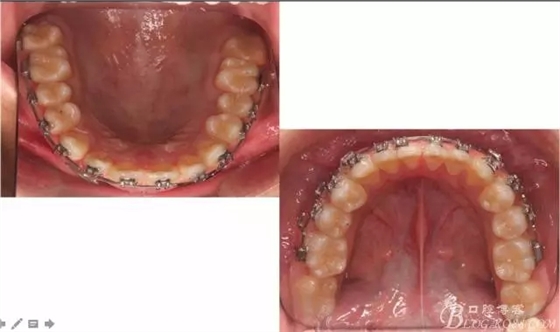

??茩z查:恒牙列,牙列式上下7-7.覆蓋二度,覆合三度,雙側(cè)磨牙關(guān)系二類,尖牙關(guān)系二類,下合3-3各牙間散在約1-1.5mm間隙,輕度唇傾,正面觀顯下頜頦部發(fā)育不足,側(cè)貌可觀察到下頜略顯后縮,上頜鼻唇角以及唇部大體正常。開口型向下,舌體正常,TMJ檢查及其它未發(fā)現(xiàn)異常。

看看口內(nèi)照吧!真象“大暴牙”v假象“大暴牙”

三度深覆合,三度深覆蓋,尖牙,磨牙均二類關(guān)系!